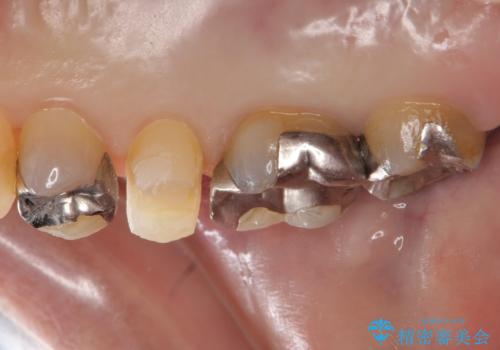

- 右上5 ゴールドアンレー 77,000円費用は治療当時の料金となります

欠けたところに金属を使用することで、再度欠けてしまうリスクを抑えました。

PGA(ゴールド)クラウン、インレーの注意事項(リスク・副作用など)

- インレーおよびクラウンは脱離するリスクがあります

- 形成量はセラミックより少ないですが、歯の形成、修復後に歯に症状が出ることがあります

- 自費診療(保険適用外治療)となります